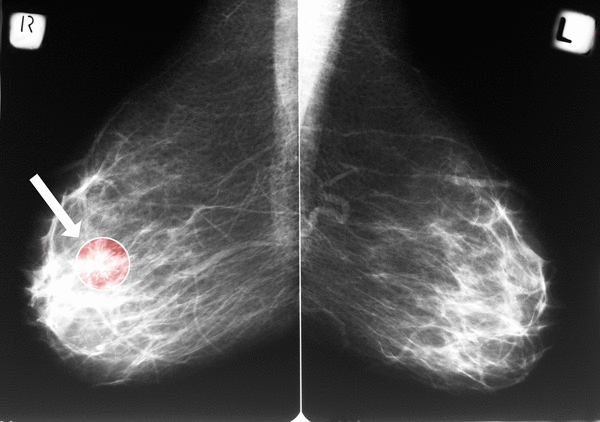

In the new Penn State study, researchers analyzed data from 10,348 women who had undergone at least two mammograms at a U.S. academic medical center, with an average of 4.1 years between scans. Using an artificial intelligence tool, the team measured the severity and progression of calcification in breast arteries over time.

They found that nearly 1 in 5 women had detectable vascular calcification at baseline. More importantly, the severity and progression of that calcification mattered. Women with worsening calcium buildup faced significantly higher risks of major cardiovascular events — up to double the risk for those with the most severe scores, Nudy explained.

In this study, researchers used AI to quantify calcification efficiently across thousands of images.

"If we were to run a research study where we had to have multiple radiologists analyze multiple mammogram images from over 10,000 participants, that would take a lot of time and a lot of money," Nudy said. AI, he added, made the process scalable and standardized.